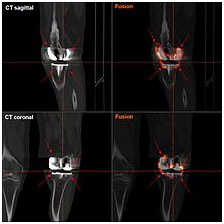

FDG-PET CT showing septic loosening of knee prothesis; the FDG-enrichment shows entensive inflammatory foci: demonstrative: the PET-image ist unlike the CT reconstruction not disturbed by the high radiation attenuation of the prothesis.